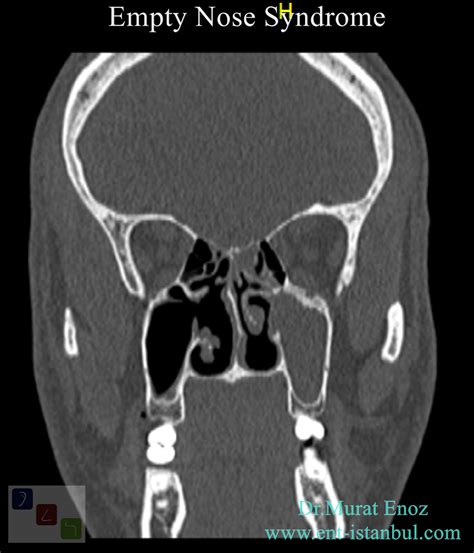

• Imaging Studies: CT scans or MRI can provide detailed images of the nasal structures and help identify any abnormalities.